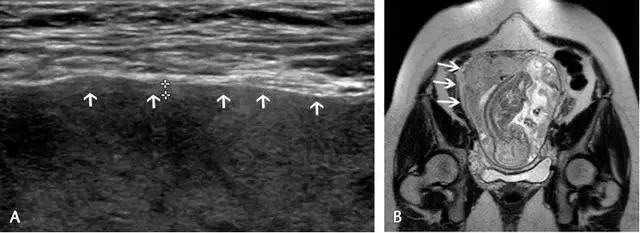

超声最早可在孕 6 周(经阴道超声)或孕 10 周(经腹部超声)显示出胎盘,表现为妊娠囊周围的薄层环状高回声。妊娠 12~13 周时,多普勒超声可显示绒毛血流。孕 14~15 周时,胎盘已充分发育,表现为显著的高回声。此时,也可看到由蜕膜、肌壁、子宫血管等组成的胎盘后复合体(图 1)。

图 1 孕 12 周时的正常胎盘矢状面,其后可见低回声的胎盘复合体(小箭头)

图 2 孕 24 周时的正常胎盘横切面,显示胎盘的回声、厚度及其后方的低回声肌壁(箭头)